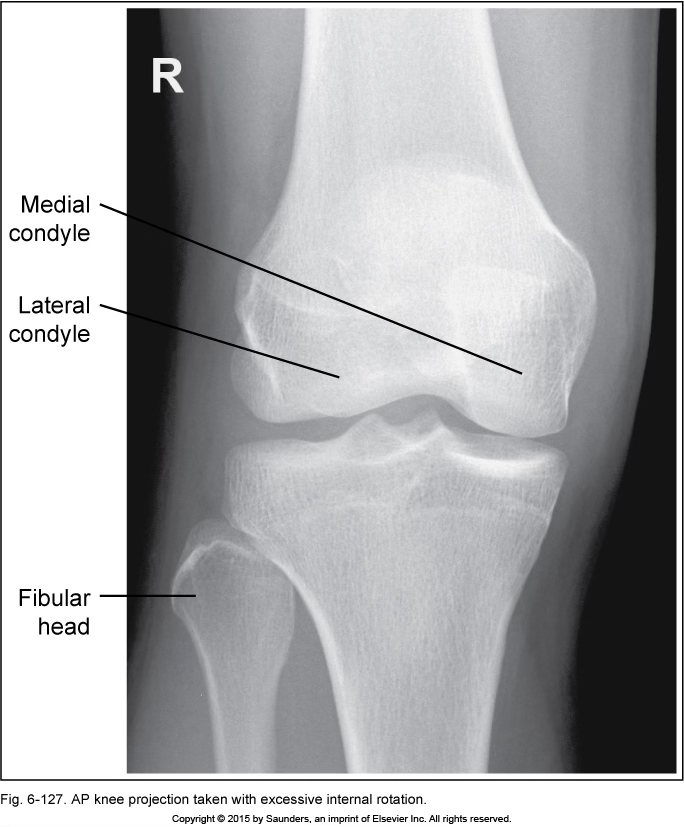

AP knee

excessive internal rotation

fibular head is too out